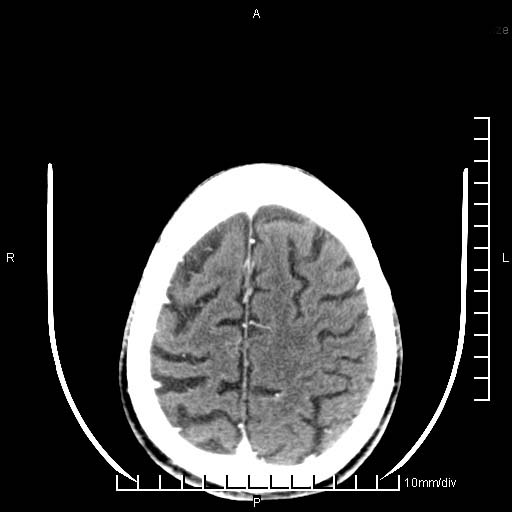

临床以双下肢浮肿,疼痛收治,无明显神经系统症状,既往无梗塞,出血病史。左颞叶见低密度灶,考虑什么?

考虑左侧颞叶脑软化灶。

无强化 无占位 软化灶吧

无强化、 无占位、局部脑沟增宽, 软化灶吧。